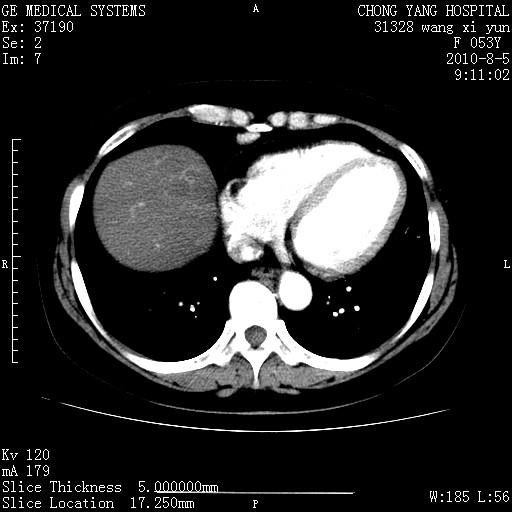

标题: CT28214:F41Y 血尿二十天,建议盆腔平扫加增强。

1)考虑肝左叶胆管细胞癌。2)脂肪肝。